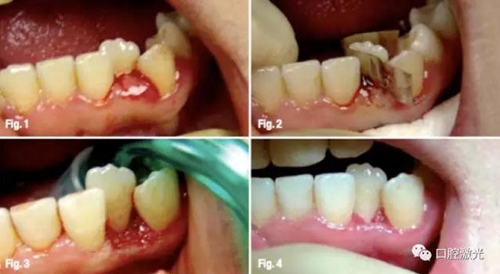

案例4 牙齦整形

27歲女性患者局部牙齦發(fā)炎。實施麻醉后進(jìn)行激光治療。為了防止對牙釉質(zhì)的損傷,治療過程中采用金屬薄片進(jìn)行防護(hù)。圖四是術(shù)后8天后恢復(fù)狀況